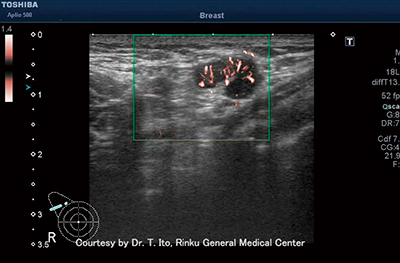

図1 乳がんのcSMI画像

腫瘤内に豊富な血流を認める。